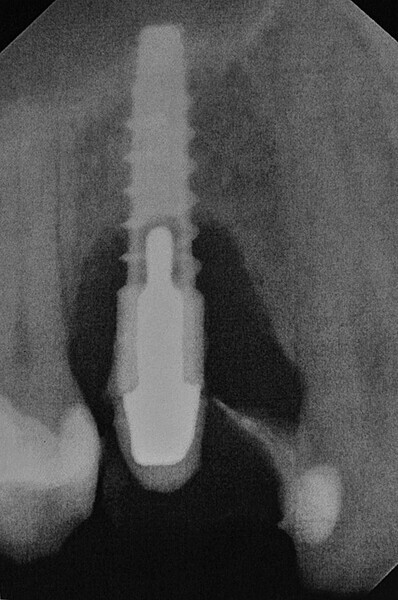

Fig. 2: Radiographic examination of the implant.